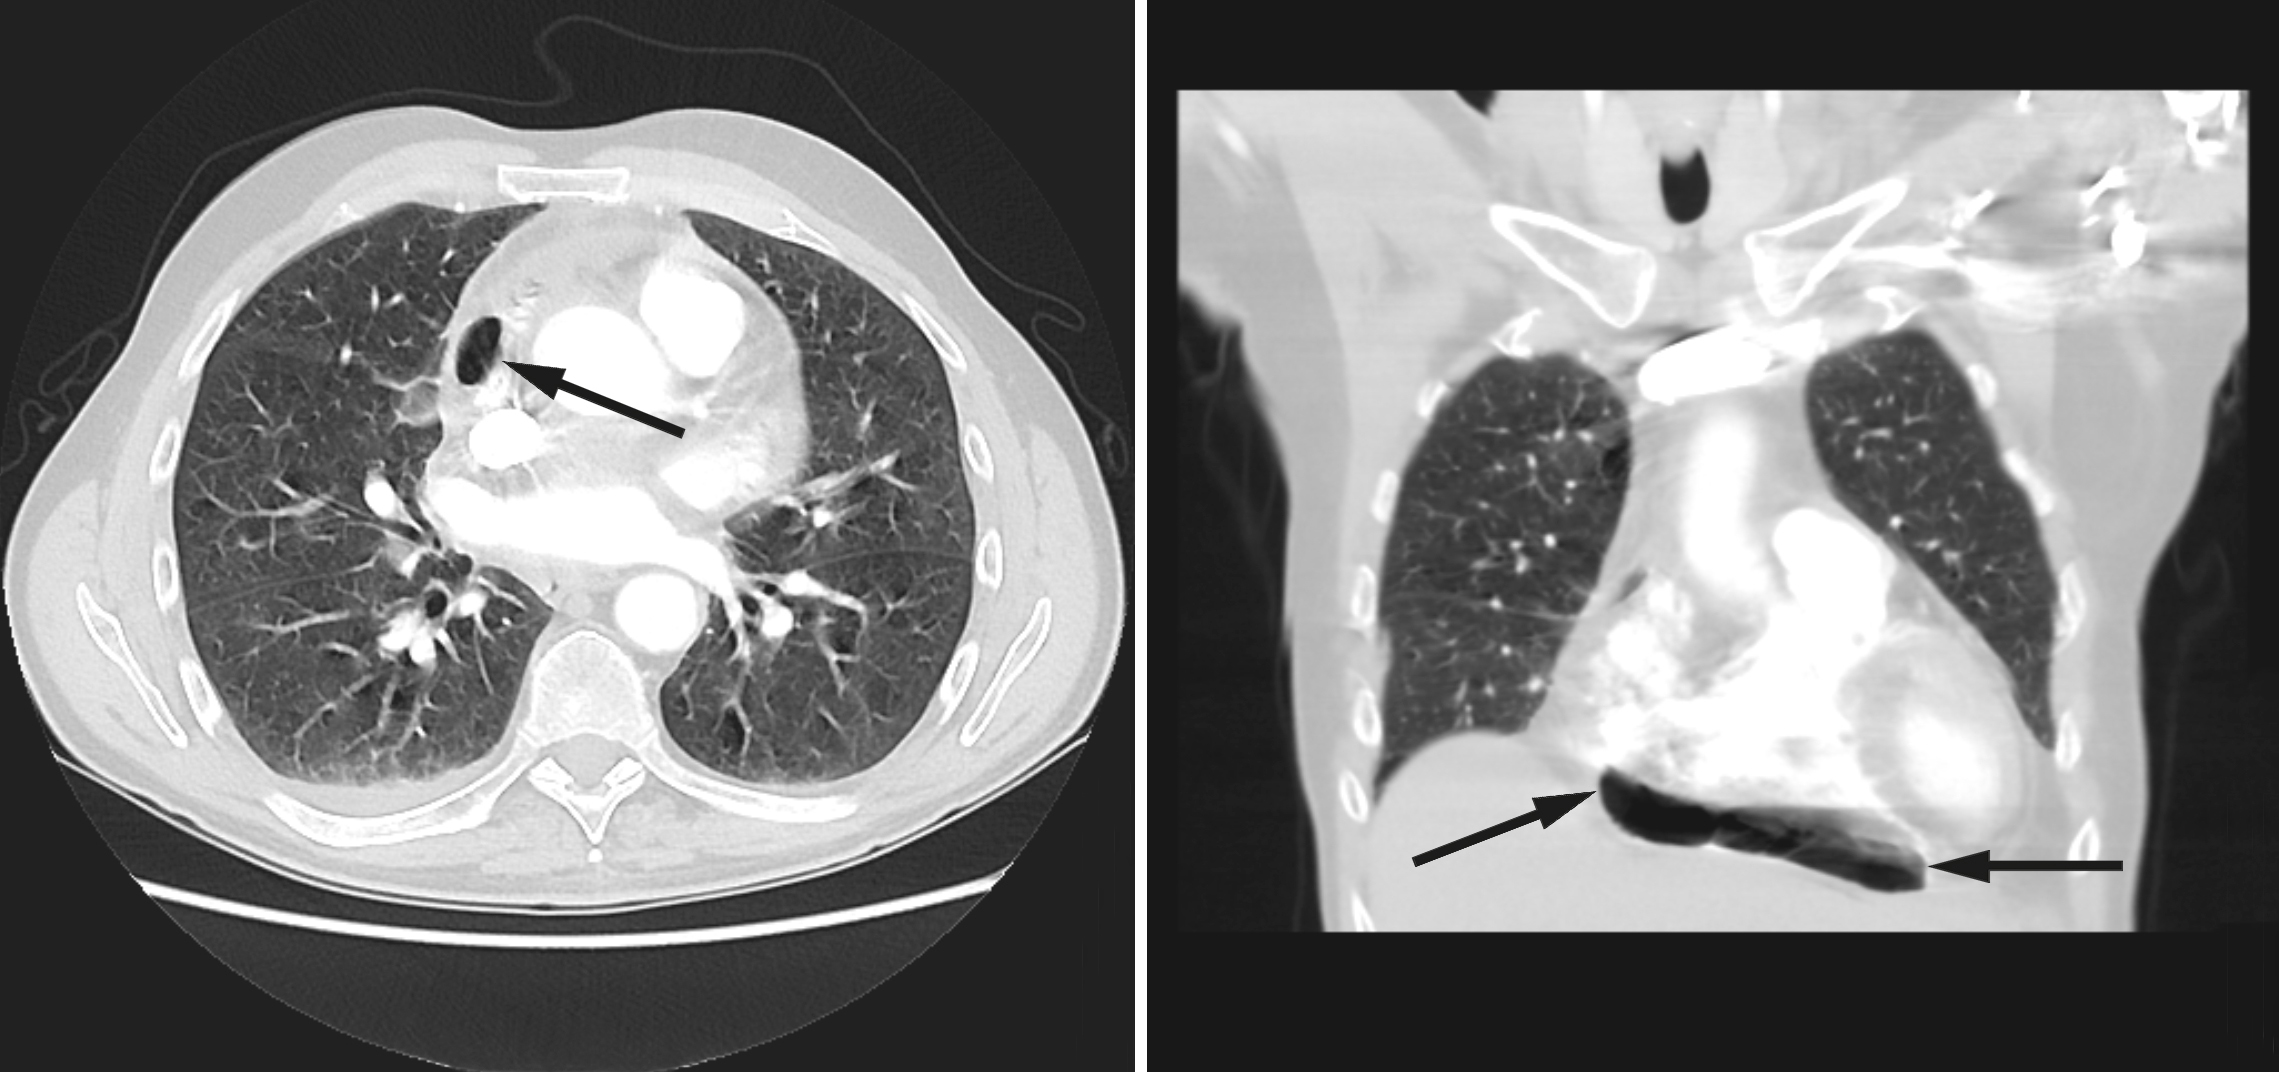

På mistanke om infeksjonsutvikling med utgangspunkt i lever/galleveier eller pancreas, ble intravenøs behandling med cefotaxim 1 g x 4 startet. Ultralyd abdomen viste slanke galleveier, men radiolog anbefalte CT abdomen for endelig avklaring. Dette ble utført samme dag supplert med CT thorax med lungeemboliserie. Underveis i denne undersøkelsen fikk pasienten akutt økende dyspné med metningsfall til 70 %, takypné med respirasjonsfrekvens på 22/minutt og takykardi med puls på 130 slag/minutt, ledsaget av kraftig forverring av smertene i høyre hemithorax. Onkolog og anestesilege ble tilkalt. Med ventilasjonsstøtte på maske klarte pasienten å gjennomføre undersøkelsen som viste fri luft i mediastinum, hovedsakelig i perikard, samt noe perikardeffusjon (fig 1). Lekkasjestedet kunne ikke påvises. I buken var det ingen fri luft.

Pneumomediastinum er definert som fri luft i mediastinum. Dette oppstår enten fordi alveoler sprekker eller fordi luft lekker fra respirasjons- eller gastrointestinalkanalen. Mediastinalt emfysem er oftest traumatisk betinget fra stumpt traume mot thorax eller iatrogent forårsaket, men kan også oppstå spontant (2). Luften kan bevege seg inn i perikardhulen, pneumoperikard, og forårsake perikardial tamponade. Ubehandlet kan dette være fatalt. Retrosternale brystsmerter som forverres ved inspirasjon og dyspné er vanlige symptomer på pneumoperikard. Ekkokardiografi kan bekrefte tilstanden og eventuell tamponade, og man kan utføre perikardiocentese for akutt avlastning. Dette gir også mulighet for biokjemisk analyse og histologi.

I foreliggende pasienthistorie var det spredning av både kreftceller og bakterier til epi- og perikard. Ved obduksjonen ble det ikke påvist økt luft/gass i perikard. Dette kan likevel ikke utelukkes, da man ikke spesifikt undersøkte for dette. Fistel mellom perikard/mediastinum og øvre gastrointestinalkanal eller trachea ble heller ikke avdekket, skjønt en liten åpning kan heller ikke utelukkes. På CT-undersøkelsen tatt dagen før dødsfallet er luft godt synlig (fig 1), men det var ikke mulig å identifisere lekkasjestedet. Sannsynligvis har maligne celler erodert perikard og epikard fra mediastinum, som ledd i det infiltrative vekstmønsteret, hvilket kan ha skapt en ventil for bakterier og luft. Fri luft/gass kunne også tenkes å ha oppstått som et (bi-)produkt av en bakteriell superinfeksjon med autolyse og vekselvirkning mellom bakterielt toksin og karsinomceller. Infeksjoner med gassproduserende bakterier i tarm eller bløtvev gir imidlertid som regel kun små gasslokulamenter på CT. Mikrobene som ble påvist er heller ikke typisk gassproduserende. Pasienten hadde ikke gjennomgått invasive prosedyrer utover biopsitakning fra lymfeknuter i øvre mediastinum, som ble utført tre uker tidligere. Denne prosedyren er rapportert å kunne forårsake penumomediastinum, men da som en akutt komplikasjon (5). Bruk av steroider og antibiotika i kombinasjon kunne potensielt forårsaket kolonisering eller infeksjon av sopp i oesophagus, med påfølgende ruptur. Det ble derimot ikke sett tegn til dette under obduksjonen. Pneumomediastinum kan utløses av kraftige hosteanfall, uten at en slik rift i luftveiene er synlig på CT. Iomeron, kontrastmidlet som gis i forbindelse med CT, kan utløse hoste, men dette er ikke journalført som et fremtredende symptom hos denne pasienten.

Retrospektivt burde bakteriell perikarditt ha vært vurdert som en differensialdiagnose i løpet av dette sykdomsforløpet. Diagnostikken ble derimot komplisert av malign sykdom og fravær av flere av de klassiske tegnene vi forbinder med denne tilstanden. Dette gjorde at bakteriell perikarditt ikke ble erkjent før obduksjonsrapporten forelå. Det er dog vanskelig å se for seg at infeksjonen i seg selv var dødelig. 100 ml puss er neppe tilstrekkelig til å forårsake tamponade, og pasienten var ikke septisk preget. Gassen i perikard truet imidlertid med tamponade, selv om det ikke var tegn til dette på CT-undersøkelsen tatt dagen før pasienten døde. Kompresjon av høyre ventrikkel kunne gi redusert slagvolum med fall i blodtrykk og takykardi, eventuelt rask atrieflimmer eller ventrikkelflimmer og sirkulatorisk kollaps. Ekko ville gitt diagnostisk avklaring, og perikardiocentese kunne ha drenert luften. Fordi vi ikke har ekko tilgjengelig på Radiumhospitalet, ville dette medført overflytting til intensivavdeling. Vi mener det kan diskuteres hvorvidt det ville vært riktig i denne situasjonen, gitt pasientens utbredte kreftsykdom og korte forventede levetid. Kasuistikken illustrerer viktigheten av bred differensialdiagnostisk tenkning ved uspesifikk symptomatologi hos pasienter med kreft. Disse pasientene har økt risiko for sjeldne og alvorlige infeksjoner og komplikasjoner. Kasuistikken belyser også en etisk problemstilling knyttet til behandling av pasienter med inkurabel kreftsykdom og kort forventet levetid: Når akutte komplikasjoner oppstår, hvor mye skal gjøres? Fordeler og ulemper ved eventuelle tiltak må vurderes nøye opp mot hverandre.